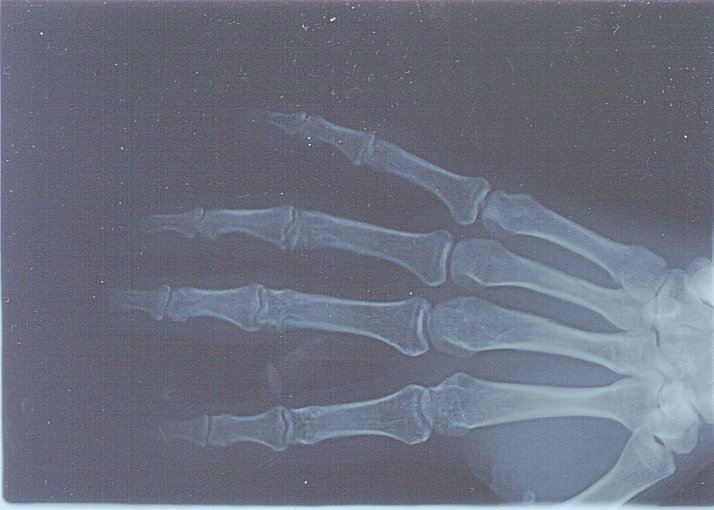

病院の先生が、レントゲンを見ながらにっこりと一言『骨折してるでぇ〜』

被害:よしりん→右手甲の骨折、字が書けないよ〜ん。服もボロボロ

事故の時に寄った病院の紹介状とレントゲンを持って、健保連大阪中央病院へ。

幸いなことに骨のずれもひどくなく、添え木で固定して様子を見ることに。